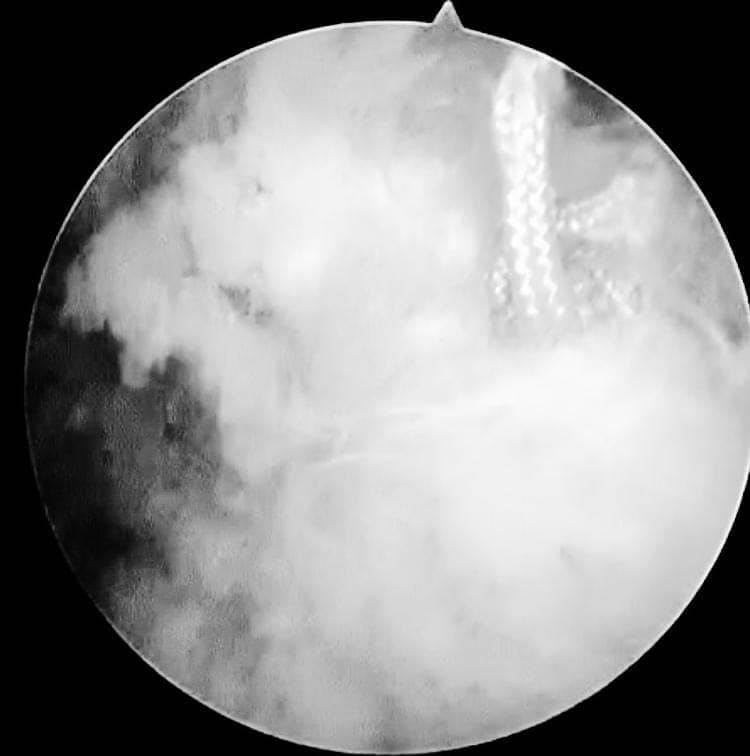

ومن جهة أخرى.. قام الدكتور أحمد إبراهيم سالم بإجراء عدد ٤ جراحات بالمنظار لعلاج مختلف إصابات الكتف مثل قطع أوتار الاسورة الدوارة للكتف وتمدد محفظة الكتف نتيجة الخلع المتكرر، وتمت متابعة المرضى لمدة ٦ أسابيع من التأهيل والعلاج الطبيعى حتى عادوا لممارسة الحياة اليومية بشكل طبيعى وبمجال حركى مقبول بدون ألم.